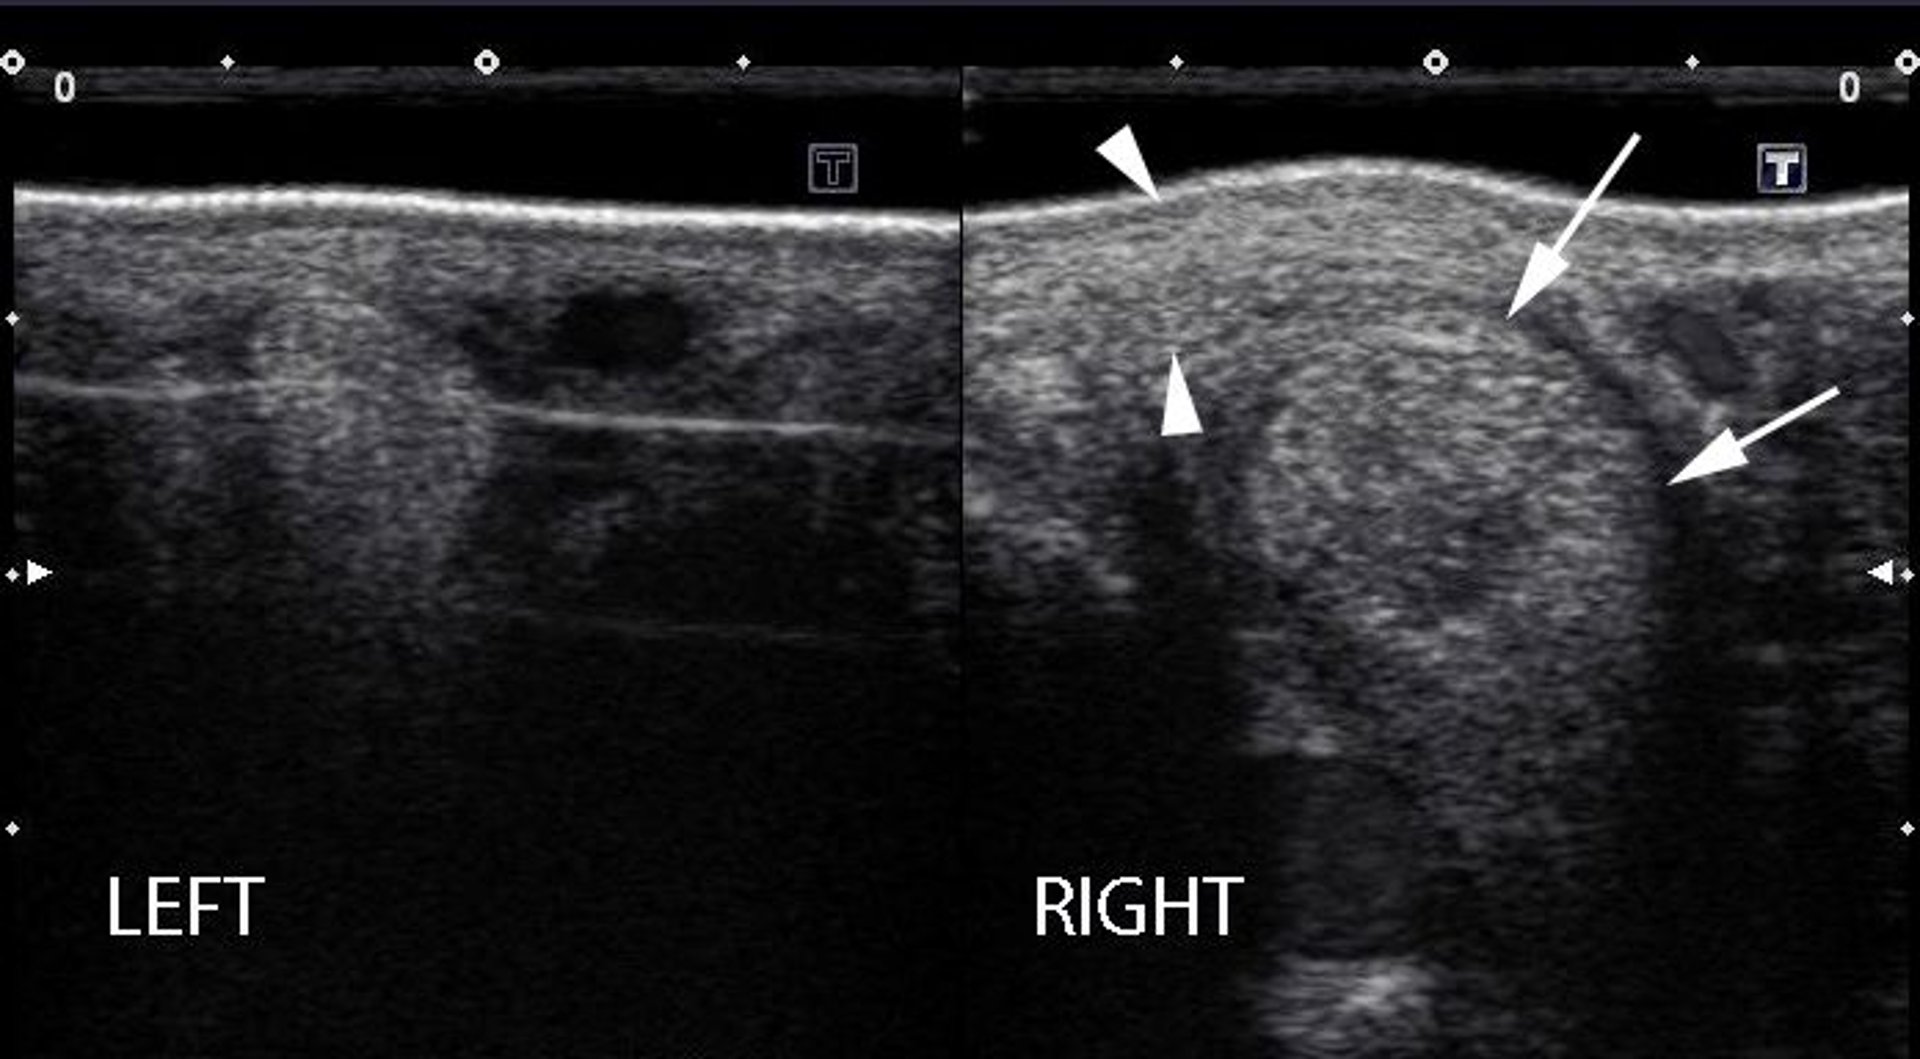

Ultrasonographic examination can reveal a range of abnormalities in the suspensory ligament branches, which might or might not be active lesions, including enlargement, alteration of shape, and alterations in echogenicity (see ).

Ultrasonographic images of the left and right medial branches of the suspensory ligament in a horse. Note the marked enlargement of the right medial branch (arrows), with hypoechoic regions present within the ligament, and marked periligamentous fibrosis around the branch (arrowheads).

Courtesy of Dr. Matthew T. Brokken.